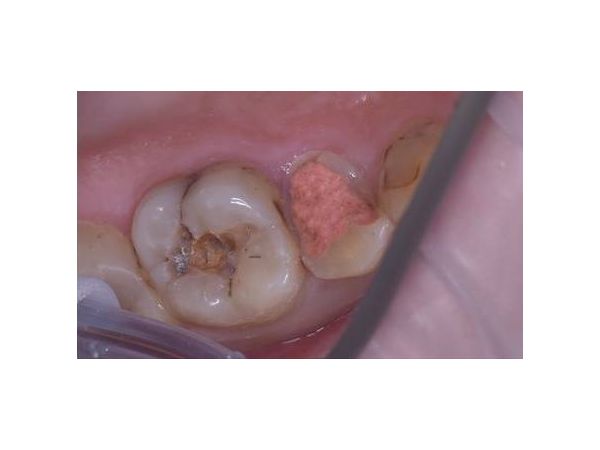

При осмотре верхних жевательных зубов справа на зубе 1.5 (премоляре) видна глубокая кариозная полость, заполненная размягчённым пигментированным дентином. Обследование дна кариозной полости стоматологическим зондом резко болезненно. Коронковая часть зуба разрушена на 70 %.

На зубе 1.6 (моляре) также имеется глубокая кариозная полость, заполненная размягчённым пигментированным дентином. Зондирование нерезко болезненно по границе эмали и дентина. Коронковая часть зуба разрушена на 50 %.